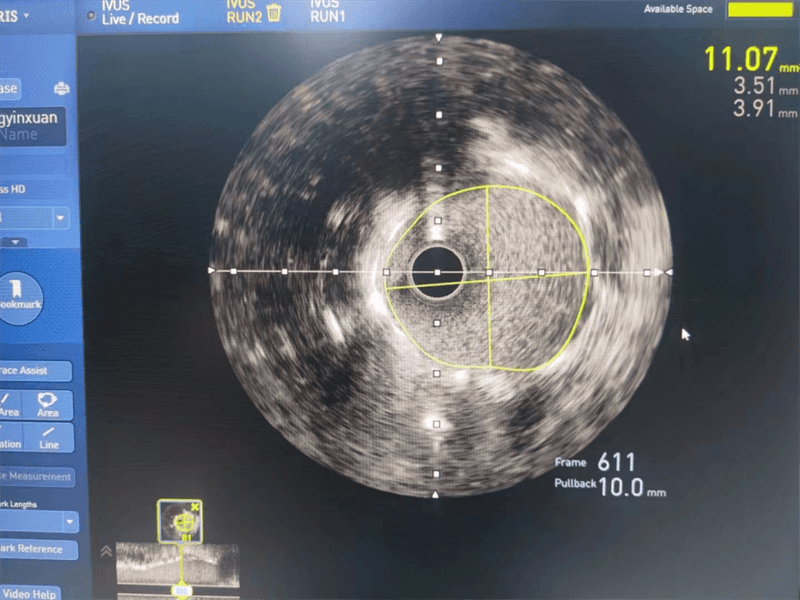

與患者家屬溝通后,其女兒猶豫不決、憂心忡忡,經(jīng)過(guò)崔主任認(rèn)真分析病情、充分溝通,征得患者及家屬同意后,為安全、精準(zhǔn)處理病變,選擇進(jìn)行血管內(nèi)超聲檢查,經(jīng)血管內(nèi)超聲檢查提示左主干至前降支近段纖維斑塊,球囊擴(kuò)張后面積3.97mm2,斑塊負(fù)荷70%,回旋支近段中度狹窄,斑塊負(fù)荷較輕。